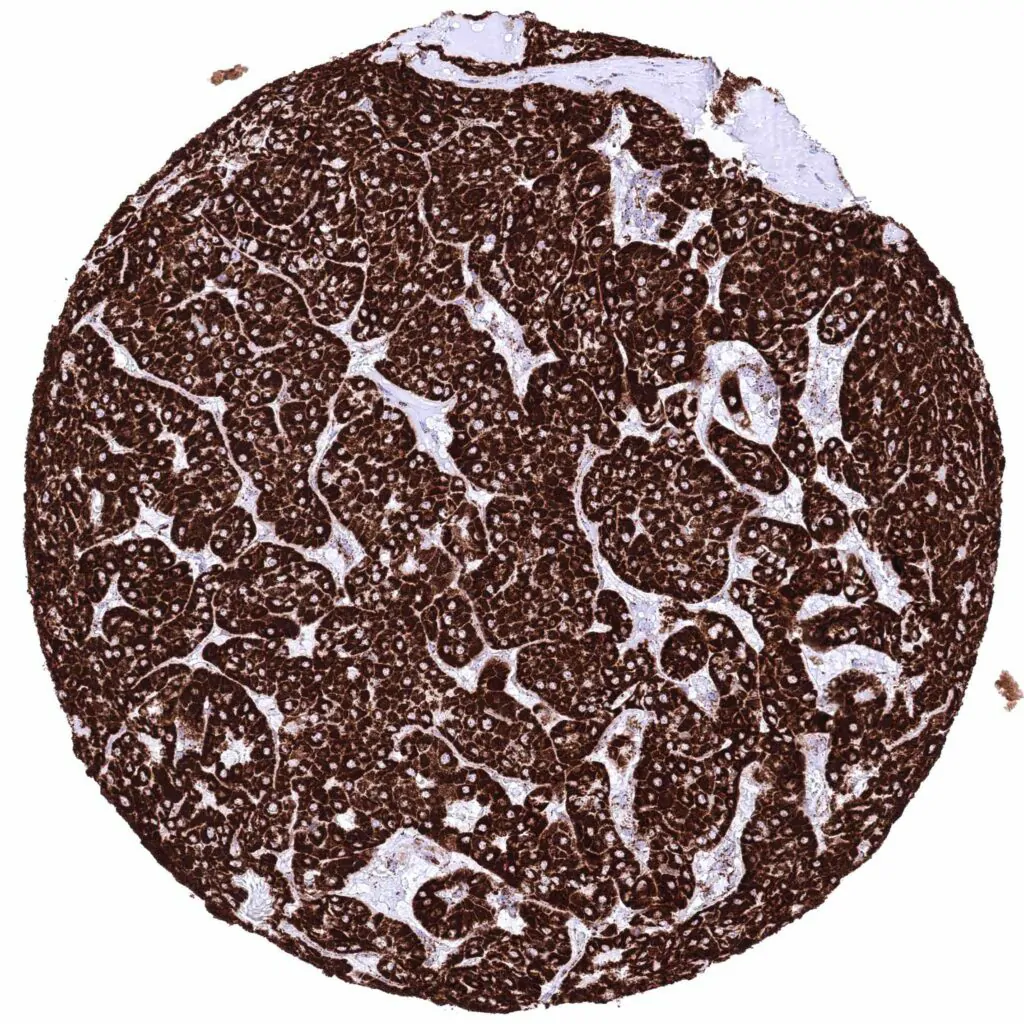

Kidney – Chromophobe renal cell carcinoma with strong cytoplasmic ATP5J immunostaining of tumor cells.